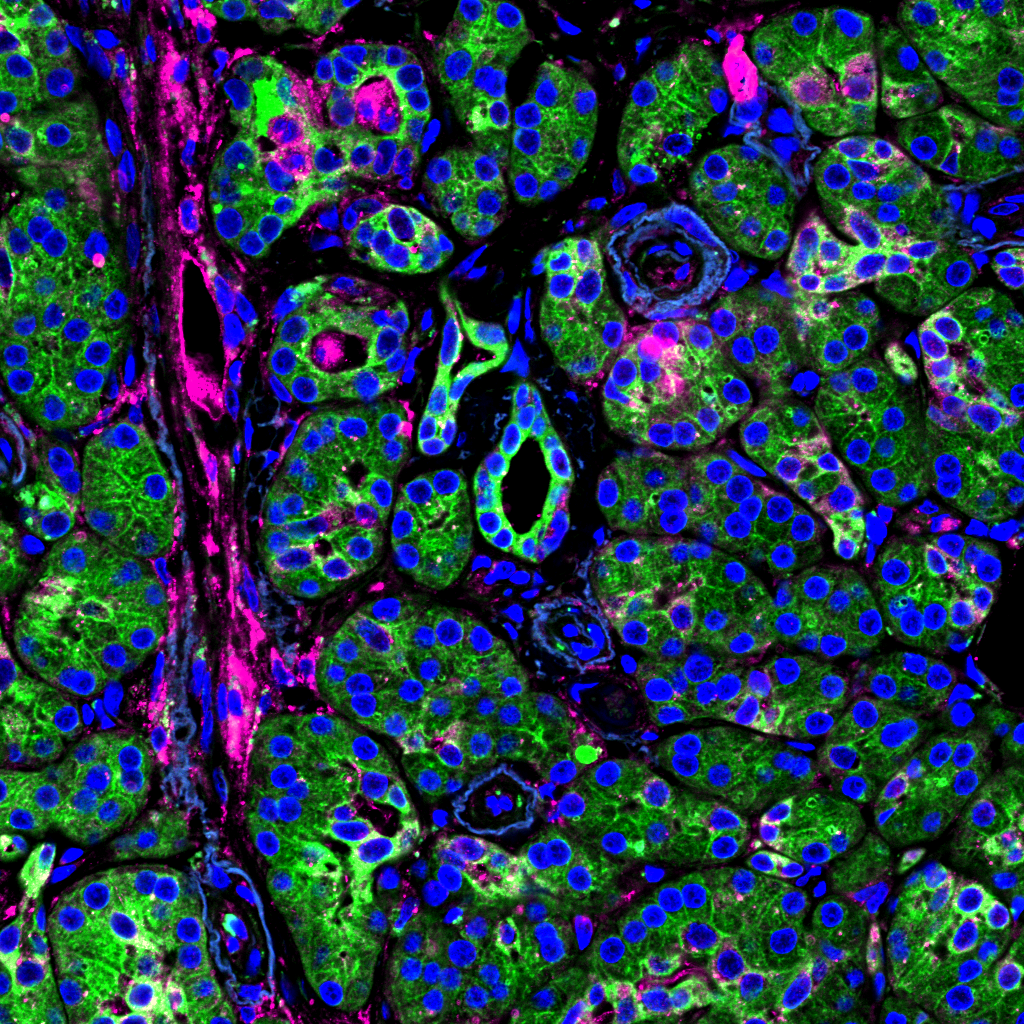

Studying how metabolism controls cancer initiation

The lab aims to uncover how metabolic changes control the earliest steps of cancer formation, with the long-term goal of identifying new strategies for cancer detection and prevention.